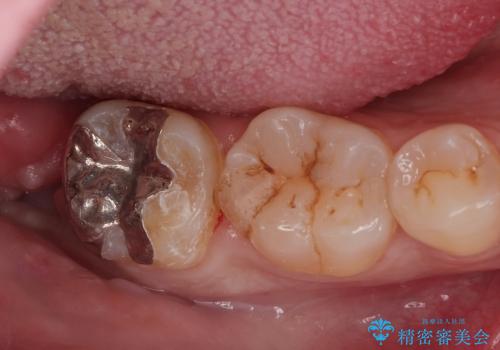

Dr. 松本麻里の症例写真

担当医 松本麻里<2026年1月14日更新>